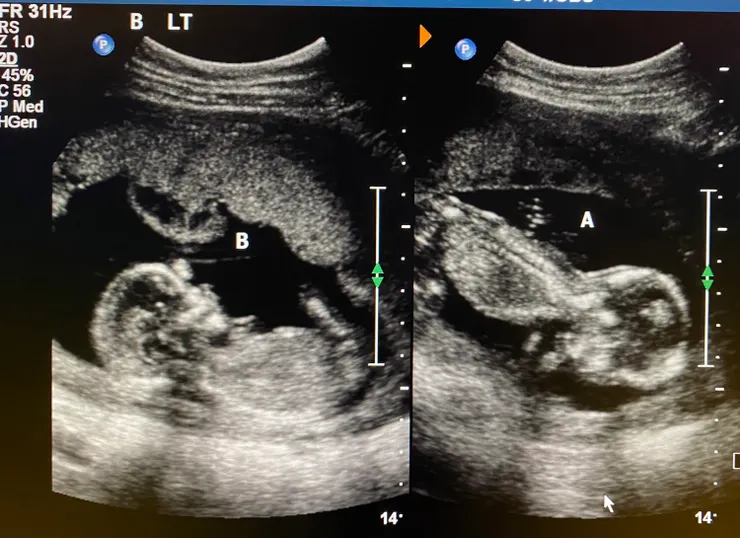

因為是同卵雙胞胎+共用胎盤,每兩週要回去一次照超音波,每次照超音波基本都半小時(起跳),由技術員操作,技術員不能告訴你任何判斷,他們也不會先看你的資料,所以第二次就發現技術員問一些上次問過的資料XD像是~預產期、這是試管嬰兒嗎、知道性別嗎、有做PGT-A嗎...等等的。有點不習慣是,這次是男技術員,第一次被男生照超音波,難免有蠻多肢體接觸,可以的話還是希望女生(默默許願)。照完超音波要去另一個櫃檯報到等醫師,這邊不同的function要到不同櫃檯,一開始不知道就在原地傻傻等,空等了不少時間。我們的醫師是Sebastian Hobson,朋友第一胎給他看,強力推薦給我們,是個專業又溫柔的醫生,這邊的醫生都不趕時間,還會跟你聊天、連伴侶也一起聊,他說希望我每天都做三十分鐘的運動,運動種類不拘,讓我更有運動的動力了,原本是一週運動3~4天,可以調整為每天!Aspirin一天吃兩顆,維生素D吃到2000IU,詢問其他問題也都詳細回答,很喜歡這位醫師,第一印象很讚。

繼續期待之後的產檢,看的小寶貝們慢慢長大。